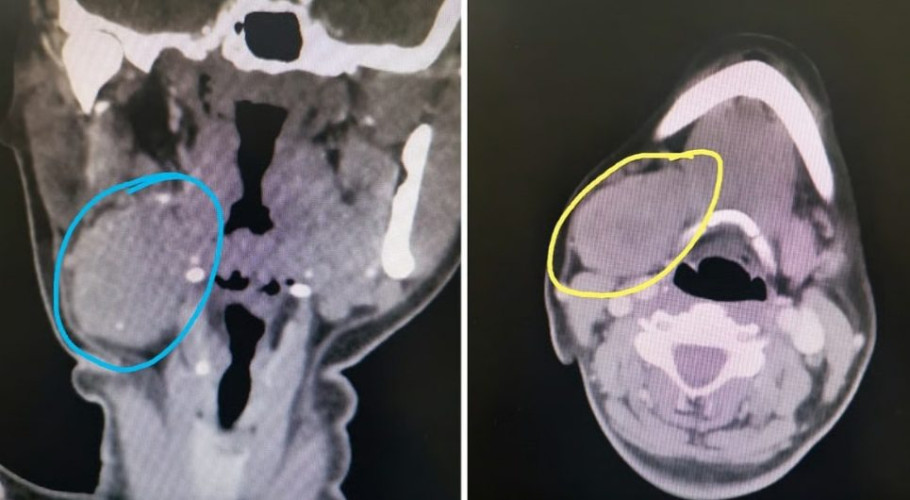

وأوضحت الفحوصات السريرية والإشعاعية التي أجريت للمريضة وجود كتلة تشمل الغدة بشكل كامل، ليتم لاحقاً اتخاذ الإجراءات الطبية اللازمة واستكمال التحاليل والتقييمات تمهيداً للعملية.

أُجريت العملية تحت التخدير العام، وتمكن الفريق الجراحي من استئصال الورم بالكامل خلال نحو ساعتين دون التسبب بأي إصابة في فروع العصب الوجهي، ودون ظهور علامات تجمع للعاب (سِيالوُسيل)، ما يُعد مؤشراً على الدقة العالية في الأداء الجراحي.